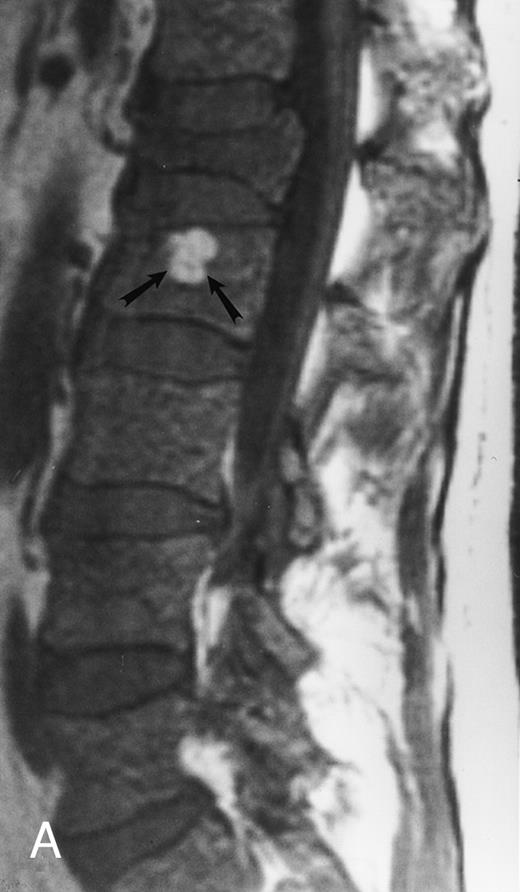

A 78-year-old woman with aplastic anemia and MR evidence of foci of hypercellular marrow. T1-weighted (500/10, TR/TE) sagittal MR image of the lumbar spine shows multiple foci of dark signal (arrows) on a background of bright aplastic marrow. On enhanced MR images (not shown), the lesions enhanced. Bone marrow biopsy showed myelodysplasia.